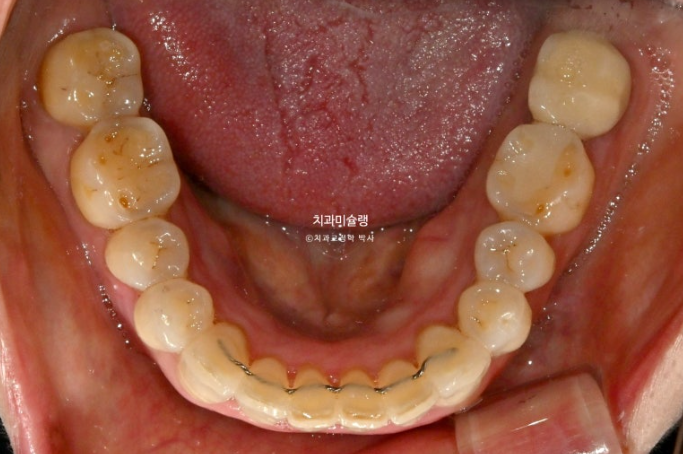

24년 7월 50대 환자분께서 교정치료를 위해 오셨습니다.

앞니가 세로 길이보다 가로길이가 더 긴, 한마디로 납작한 형태입니다.

치아 사이사이 벌어진 틈을 레진으로 메꿔놓고 지내온 것입니다.

충치로 인해 어금니들을 발치하게 되면서 교정치료를 병행하고자 오셨습니다.

일단 앞니 사이사이 레진을 제거해 보았습니다.

아래 앞니 사이 치석도 같이 제거합니다.

레진이 차지하는 비중이 컸습니다

아래 앞니 사이사이는 공간이 없는 데 위 앞니 사이사이에만 큰 공간이 있다면

이 공간을 교정으로 100% 메꿀 수 없습니다.

최대한 공간을 줄여놓고 남은 미세공간은 레진으로 마무리 해야 합니다.

인비절라인 라이트 치료 권유드렸습니다.

아래 앞니는 원래 있던 블랙트라이앵글을 없앨 겸 치간삭제를 동반하기로 합니다.

또한 아래 앞니가 위 앞니를 밀어내어 위 앞니 벌어짐이 심해지지 않도록 아래 앞니는 함입도 필요합니다.